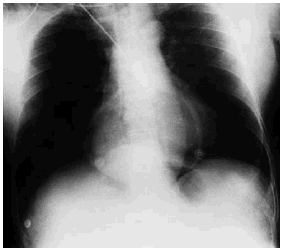

Mujer de 72 años sin antecedentes de interés, que ingresó en la Unidad de Cuidados Intensivos tras politraumatismo secundario a atropello. En los estudios radiológicos simples se objetivó fracturas de ambos fémures y de cúbito derecho, así como fracturas costales derechas junto con neumotórax y contusión pulmonar ipsilateral. Llamó la atención en la radiografía simple de tórax la presencia de una burbuja de aire a nivel centromediastínico (fig. 1). En la tomografía de tórax se observó que parte del estómago se encontraba en el tórax, retrocardíaco (fig. 2). El antro gástrico era intratorácico y aparentemente el fundus se encontraba infradiafragmático (fig. 3), lo cual fue interpretado como hernia paraesofágica postraumática. La paciente fue intervenida quirúrgicamente de urgencia; el estómago estaba contenido en un gran saco herniario con un vólvulo mesenterio axial. Había un gran orificio diafragmático. Se procedió a la reducción y devolvulación, así como a la extirpación del saco peritoneal, con funduplicatura de 360° y oclusión posterior del orificio hiatal. La paciente evolucionó favorablemente, y fue dada de alta de la UCI a los cinco días del ingreso.

Figura 2.